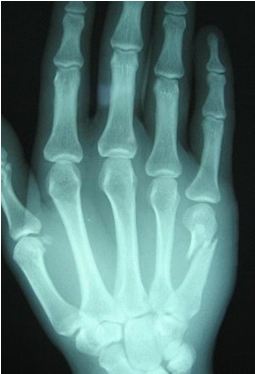

توجه بهظاهر و محل کیست معمولاً برای تشخیص کیست گانگلیون کافی میباشد. علاوه بر این در هنگام معاینه جسمی بهوسیله چراغقوه بر روی کیست نور انداخته میشود. ممکن است پزشک جهت تائید تشخیص خود از مایع درون کیست نمونهبرداری کند. عکسبرداری اشعه ایکس غالباً در مواردی استفاده میشود که پزشک به وجود مشکلاتی نظیر استئوآرتریت (ورم مفاصل و استخوانها)، خارهای استخوانی، تومورهای استخوانی یا انواع شکستگی مشکوک باشد. بااینحال میتوان از عکسبرداری اشعه ایکس جهت تشخیص آسیبهای واردشده به استخوان مچ دست براثر کیست استفاده نمود.